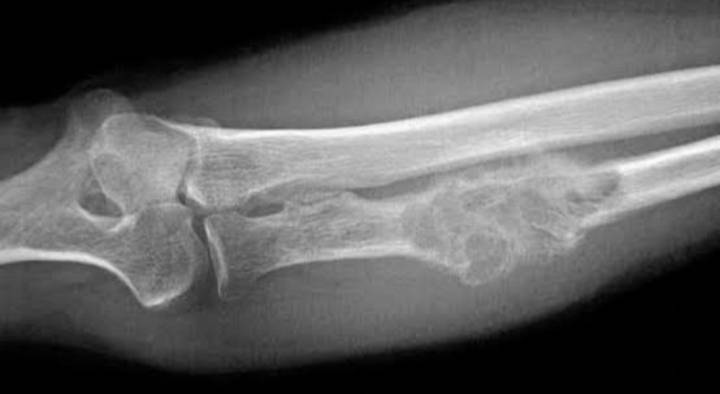

A family is appealing for help as their young daughter, Dianne, requires immediate medical care for osteosarcoma, a serious form of bone cancer affecting her knee. According to her parents, the diagnosis has placed an overwhelming emotional and financial strain on the household, as treatment costs continue to rise beyond what their current income can support.